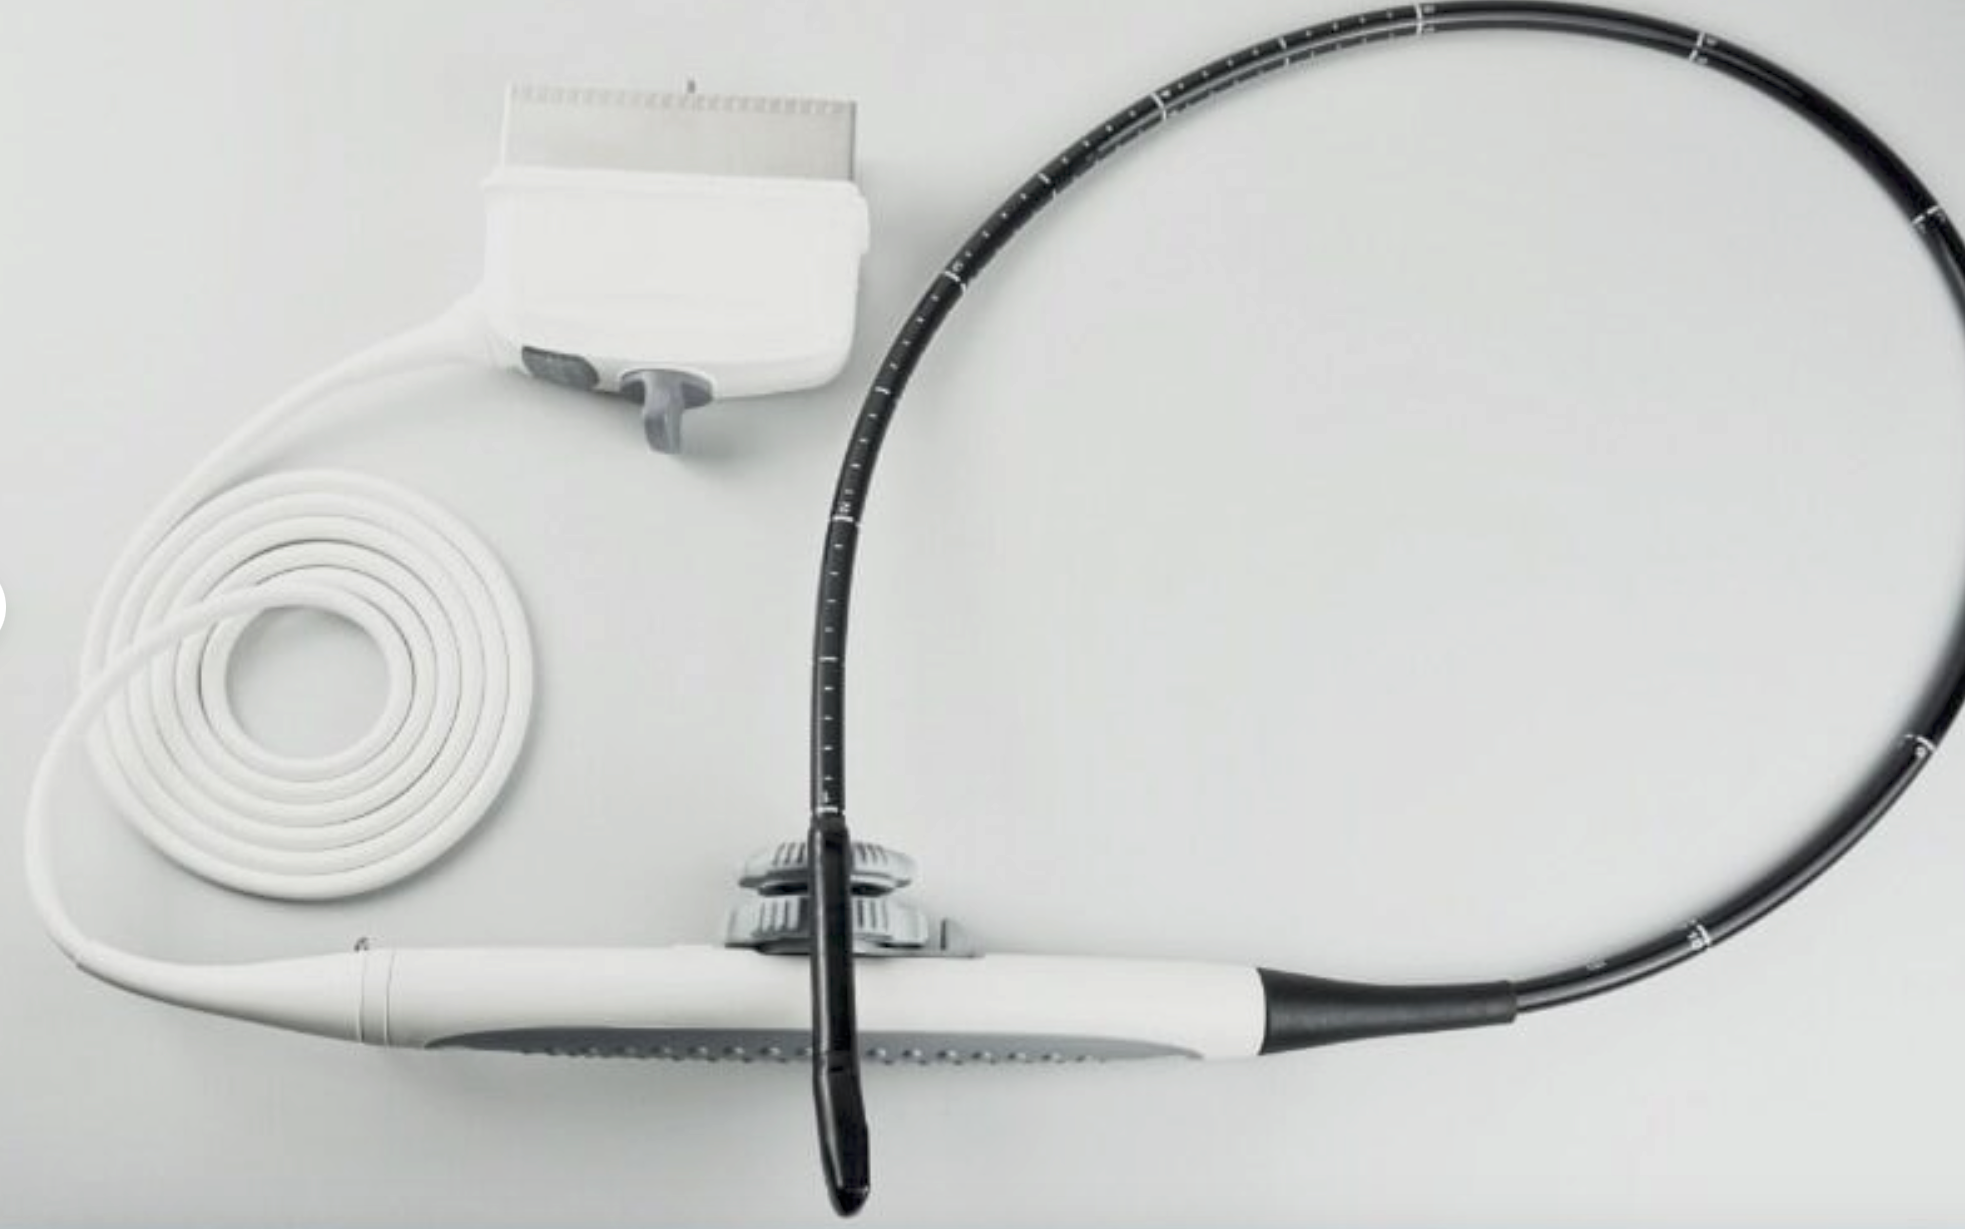

Veterinario Touchscreen Ultrasoundµ-convex Sonda per S Animali, Keebomed

- Modello: KeeboTouch 20V

- Viene fornito con una micro sonda convessa 5,5 / 6,5 / 7,5 / 8,5 MHz.

- La sonda rettale ha una lente da 65 mm e ha un cavo lungo.

- Questa macchina ha 3 connettori per sonda, quindi è possibile collegare 3 sonde contemporaneamente.